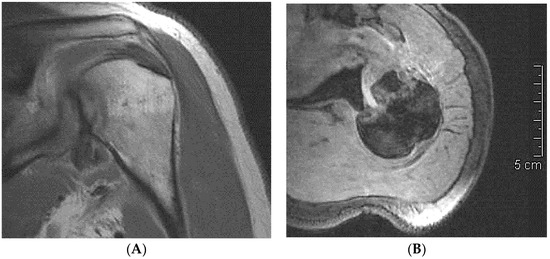

| 1 CP | M–49 | 19 days | 22 days | Hill–Sachs reverse lesion <50% | McLaughlin technique Subscapularis tendon transfer |

| 2 DF | F–49 | 70 days | 106 days | Hill–Sachs reverse lesion <50% | Subscapularis tendon transfer |

| 3 AA | M–54 | 6 days | 14 days | Hill–Sachs reverse lesion <50%, humeral insertional detachment of ST and LHB | Subscapularis tendon transfer |

| 4 CI | M–34 | 2 days | 9 days | Hill–Sachs reverse lesion <50% | Repair through a plication of subscapularis tendon (McLaughlin modified technique) |